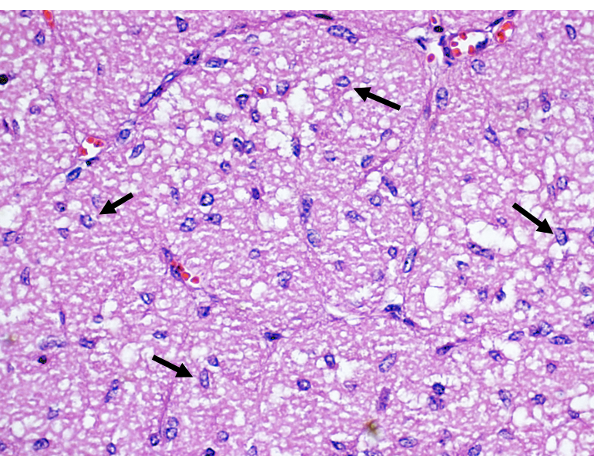

24

Q

A

Zona glomerulsoa

25

Zona fasciculata